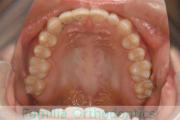

No.23V-061

- 主な症状:

- 叢生

- その他の症状:

- 上下顎前突

- 年齢:

- 23歳

- 性別:

- 女性

- 抜歯部位

- 上:

- 44

- 下:

- 主な使用装置:

- FEA 022

- 治療にかかった費用:

- 88万円

でこぼこを綺麗に並べたいということで来院されました。上下左右から小臼歯を抜歯して、マルチブラケット法を2年半、30回程度通院していただいて行いました。

かなり強い叢生(でこぼこ、凹凸、ガタガタ)のため、保定をしっかりしないと後戻りのリスクが高いケースといえます。

- ≫治療前

-

上顎

下顎

前歯の関係など

右側

正面

左側

- ≫治療後